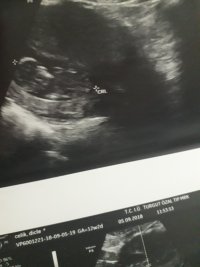

Nub teorisiyle cinsiyet tahmini bebeğim erkek mi kız mı ?

Banada yorum.yapin lutfen 12 haftaligiz

Nub teorsisi için cinsiyet tahmininde yorum isteyen arkadaşlar lütfen uyarımızı dikkate alın. Ultrason görüntüleri elinize ilk verildiği gibi net olmaz. Sık sık ışığa maruz kaldığı için görüntü kalitesi bozuluyor dolaysıyla bizlerde değerlendirme yapamıyoruz. Sizlere yorum yapabilmemiz için görüntü kalitesi aşağıdaki linkte yer alan görseller gibi olmalıdır. Ayrıca Bebeğin cinsiyeti net olarak 18-19-20. haftalarda belli olur..

Merhaba, yüklediğiniz görsellerde nub çıkıntısı anlaşılmıyor , dolaysıyla değerlendirme yapamıyoruz.. Görselin kalitesi aşağıdaki gibi olmaldır.. Sağlıklı gebelik süreci diliyorum.